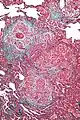

High magnification micrograph of hypersensitivity pneumonitis showing granulomatous inflammation. Trichrome stain.